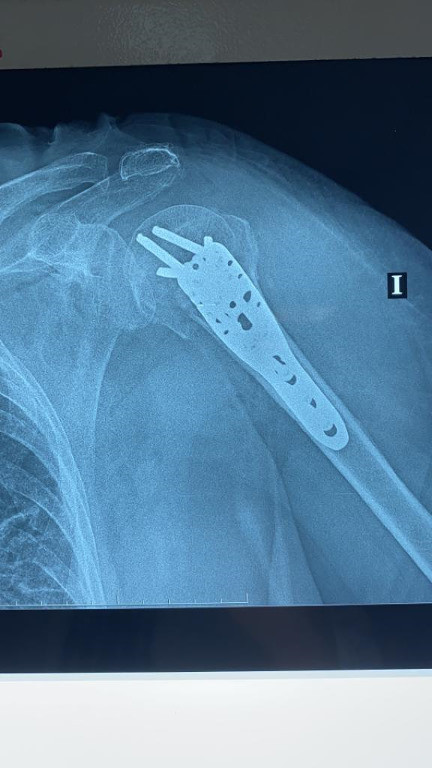

Imágenes de ortopedia y traumatología

Envíado por Dr. José Israel Flores Hernández